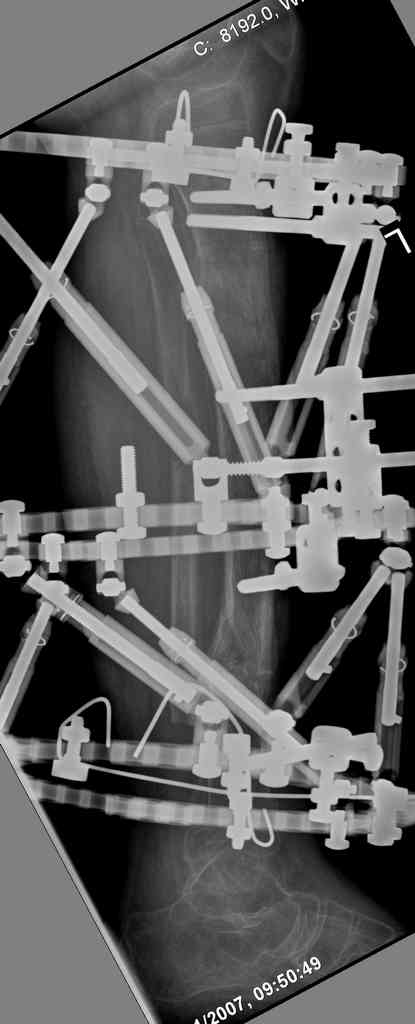

5. Ну и чтобы не быть голословным. Молодой человек подорвался на фугасе (Чечня, 2005 год). Свежие рентгенограммы:

Соответственно ожоги и дефект мягких тканей, переломы костей стопы и пр. Наложили аппарат

Илизарова (как придется), хирургически обработали и героически заживляли мягкие ткани с многочисленными кожными пластиками. В итоге через полгода я принял его вот таким:

Реализовал описанную выше методику, и в итоге вот что получилось. Высылаю лишь прямые проекции,

в боковых тоже всё в тему.

Очень пригодились карбоновые кольца (Джолдас -огромное спасибо, я твой должник!!!), поскольку остеопороз дистального отломка был просто невероятный. На цифровом рентгене с трудом угадывались контуры.

Рентген в процессе перемещения - внизу карбоновые кольца, тракция фрагмента спицами с упором.

внешний вид в аппарате - не завершающем этапе, сначала стопа тоже была фиксирована в аппарате.

Сейчас аппарат сняли, но случай ещё не завершенный.

Признаюсь честно, не совсем уверен в прочности консолидации на стыке косточек. Кроме того, укорочение в районе 6 см. Сейчас реабилитация - ходит опираясь на ногу с одним костылем.

Продолжение, видимо, будет... Возможно, будем удлинять.